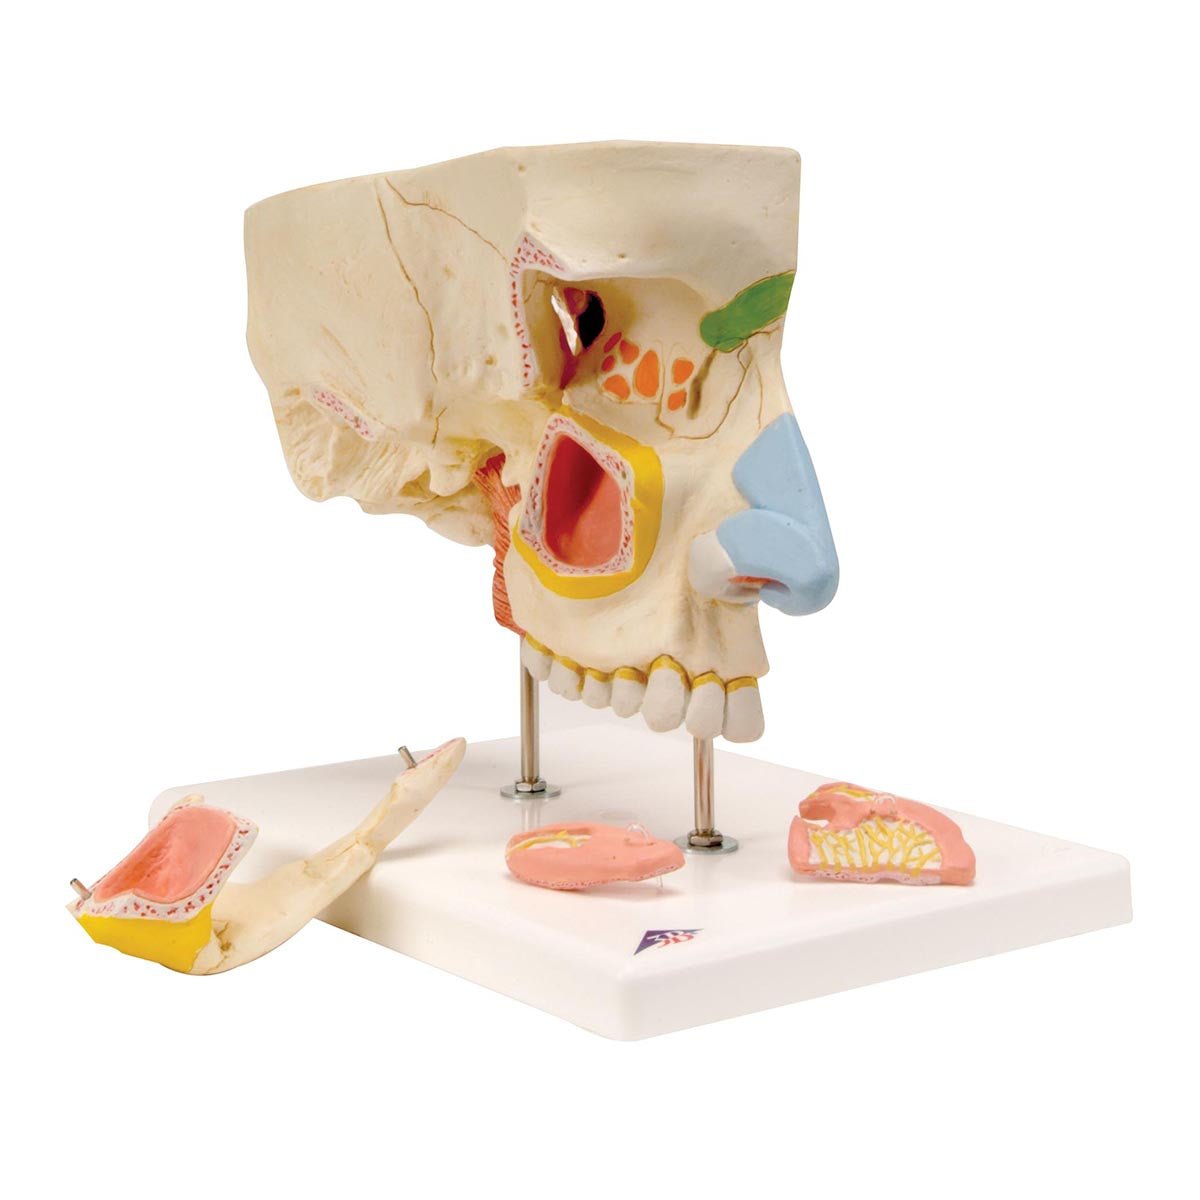

Salg af anatomiske modeller er det bærende element i eAnatomi, selvom vi også bruger mange ressourcer på at udvikle vores egne anatomiske materialer som fx plakater. Anatomiske modeller anvendes til forskellige formål og kan både vise afgrænset væv, organer samt organsystemer. Søger du en simpel model af knoglevæv eller måske en avanceret torso-model baseret på MRI teknologi, kan du finde det hele på eanatomi.com.